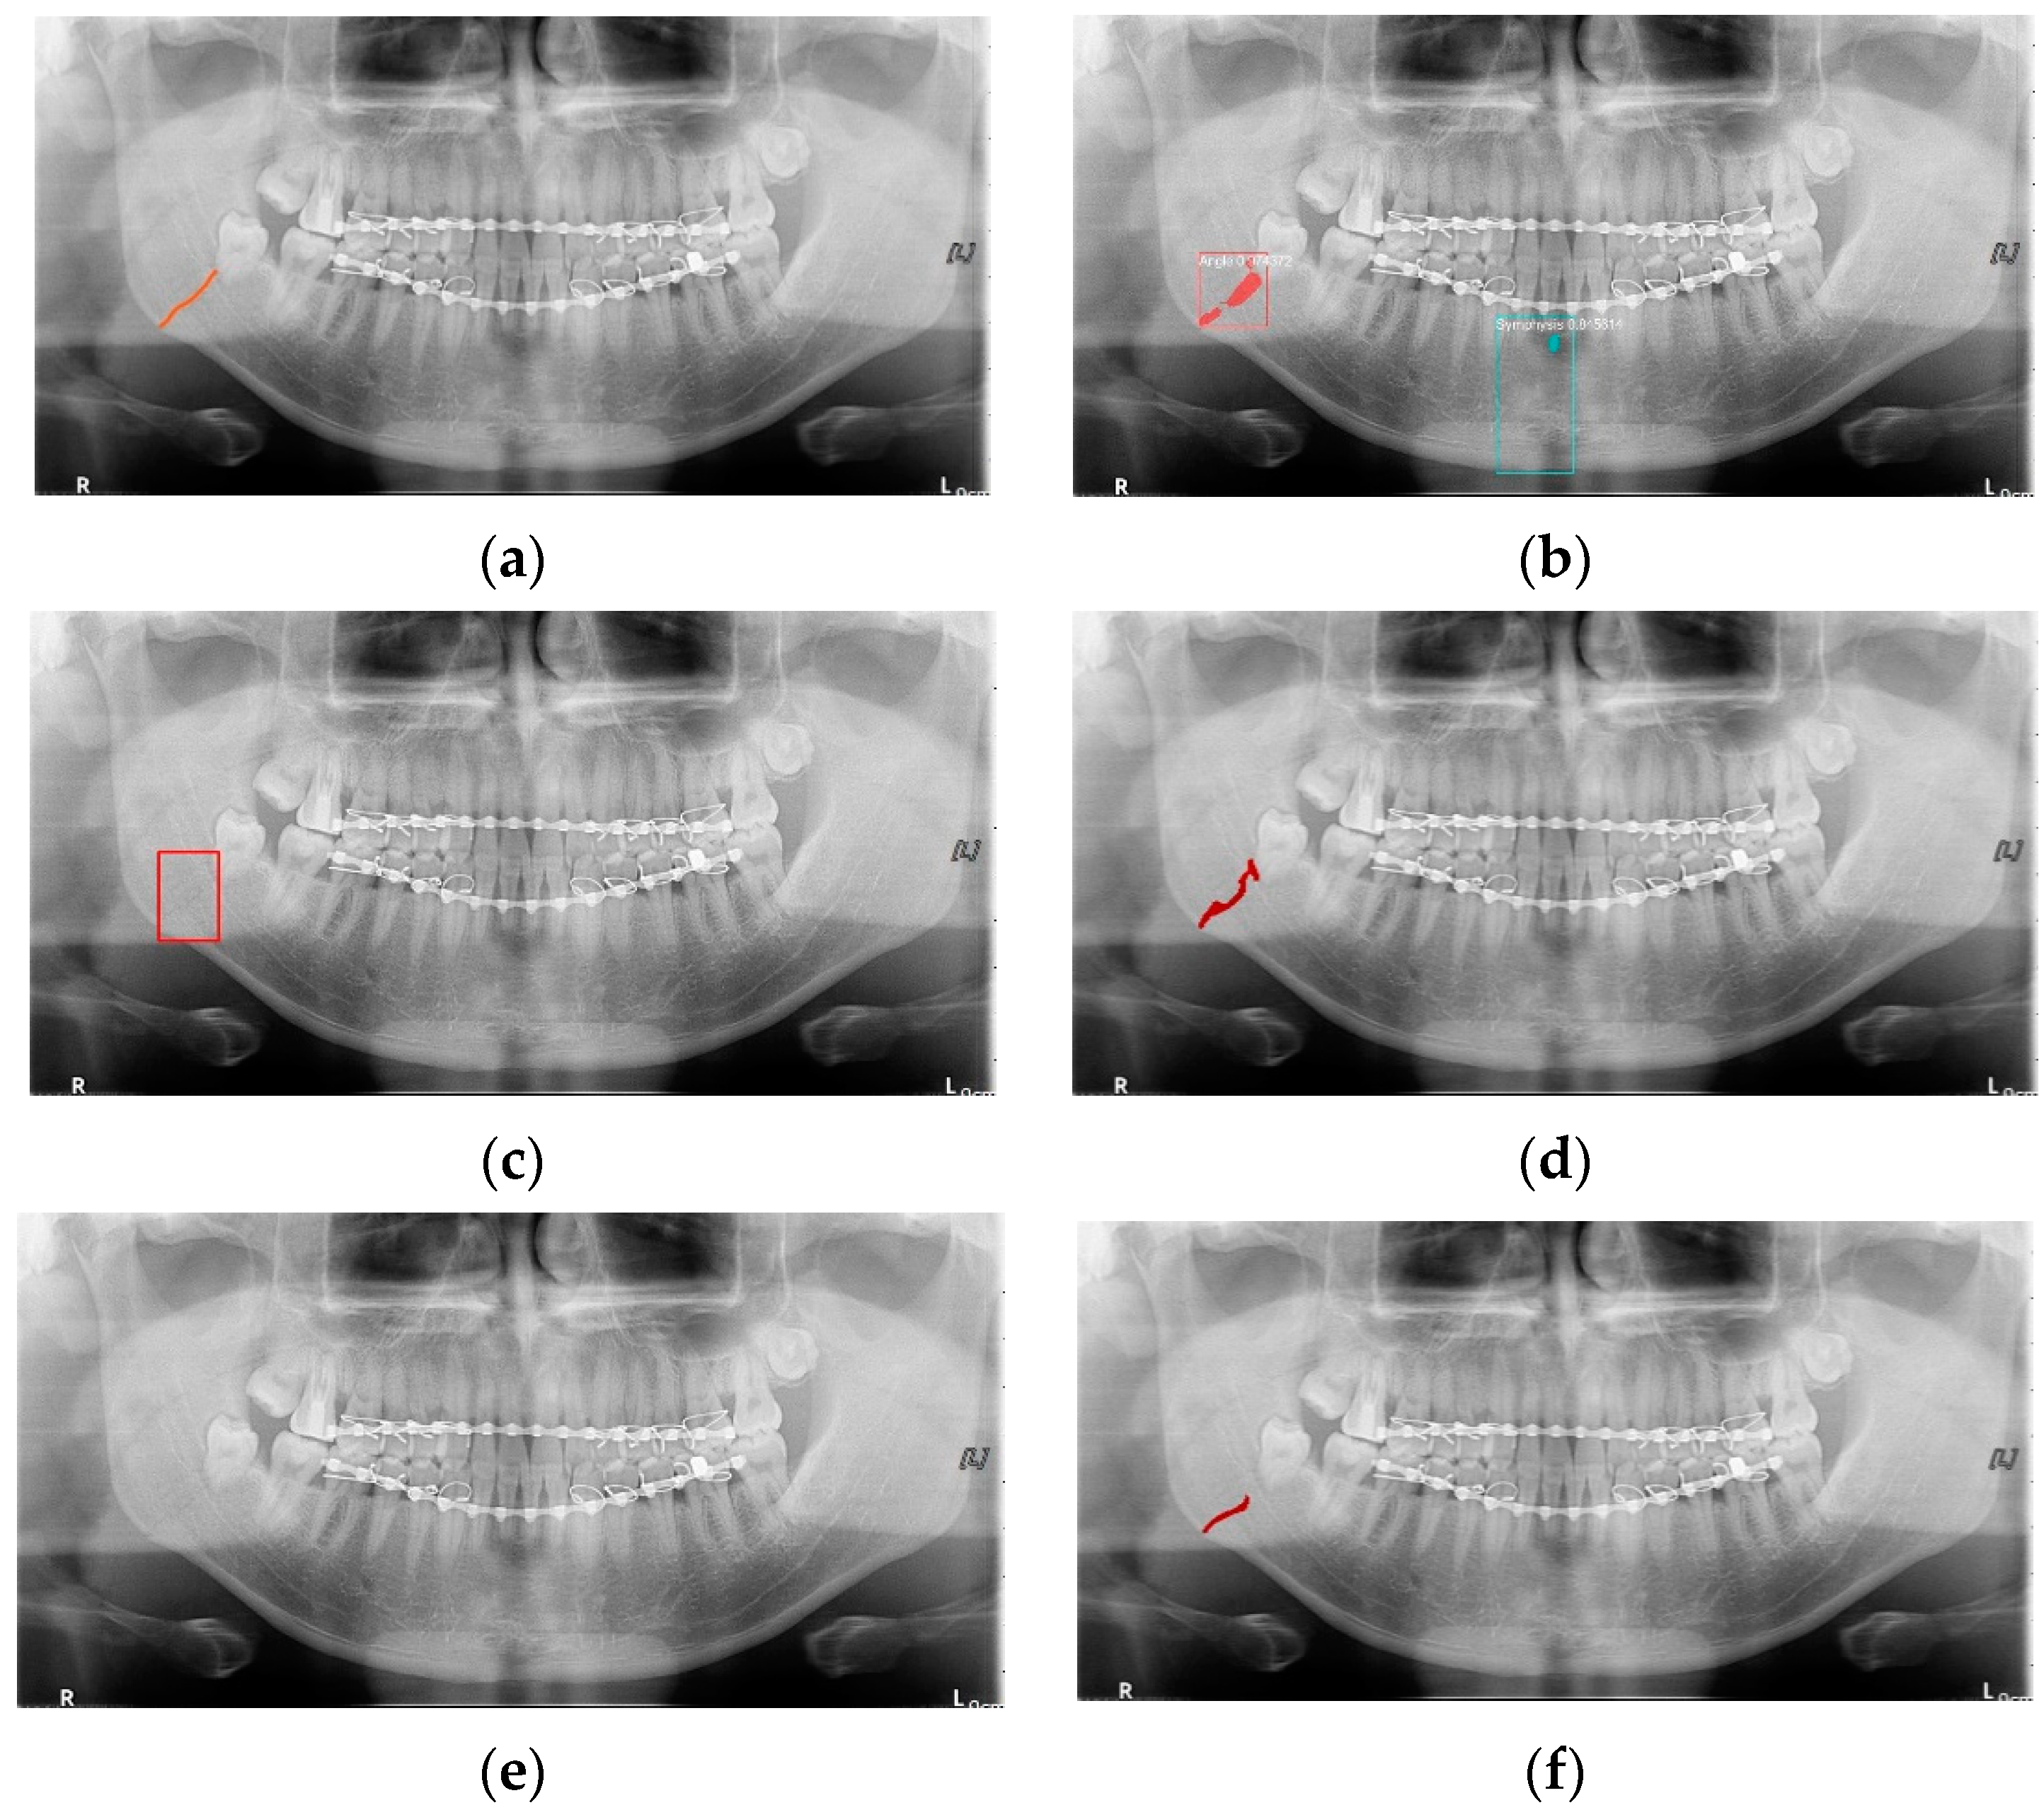

YOLO, Mask-R-CNN, and U-Net use different data-segmentation methods when constructing the training data. First, the mandibular fracture diagnosis module using Son et al.’s LAT YOLOv4 has a good diagnostic ability for fracture positions; however, it has a high undetected rate because it does not accurately distinguish fracture shapes and expresses fracture areas in the form of boxes. This module shows the diagnostic performance of precision of 97%, recall of 79%, and F1 score of 88%. In particular, fractures in the symphysis, body, angle, and ramus tend to be distributed in the middle of the mandible, and undiagnosed detection errors increase owing to irregular fracture shapes and overlapping location information. The advantage of location information is weakened; there is the possibility of a case where a fracture that is visible to the naked eye cannot be detected (Figure 3b). Therefore, additional applications such as Mask R-CNN, which is another object detection deep learning, and U-Net, which is used for medical image region segmentation, are needed to improve detection capabilities, especially recall scores representing undiagnosed performance in existing studies.

Figure 3.

The result of mandibular fracture detection: (a) diagnosis by oral and maxillofacial radiologist, (b) by LAT YOLOv4 module (with red boxes), (c) by Mask R-CNN (with colored polygons and boxes), and (d) by U-Net.